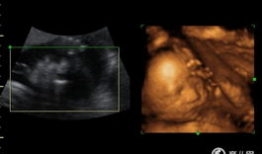

四维视频,四维视频揭示的视觉奇观与未来科技展望

哇,你有没有想过,未来看电影会是什么样子?想象你戴上眼镜,眼前不再是平面的画面,而是一个立体的世界,仿佛你真的置身其中。这就是四...